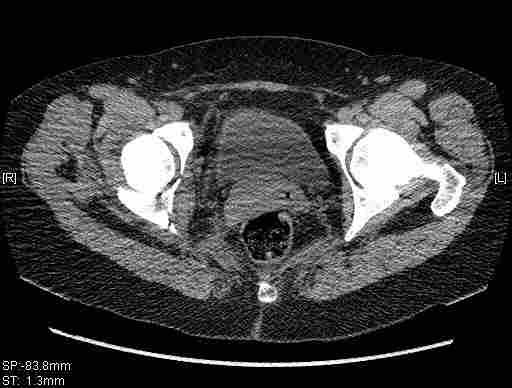

имеется передний подвывих, головка нагружаемой зоной будет "тереться" о край фрагмента, связанного с осевым скелетом.

вероятность быстрого прогрессирования коксартроза велика, хотя вряд ли кто-то укажет конкретные сроки. 1 год - 1,5 ?

Уважаемый Коваленко А.Н., снимки плохого качества и нет уверенности, что задняя колонна сломана (смещена). Если кт нет - везите больную в рентгенкабинет (палатником качественные снимки снимки не получатся) и сделайте обзорный снимок таза, Judet и может быть inlet, хуже вы ей не сделаете.

Вытяжение не поможет в любом случае, т.к. потянуть за одну переднюю колонну не получится. Есть вариант закрытого лечения, но для этого нужно наоборот сдавить крылья (скажем аппаратом), если больше переломов переднего полукольца нет, то передний подвывих уменьшится.